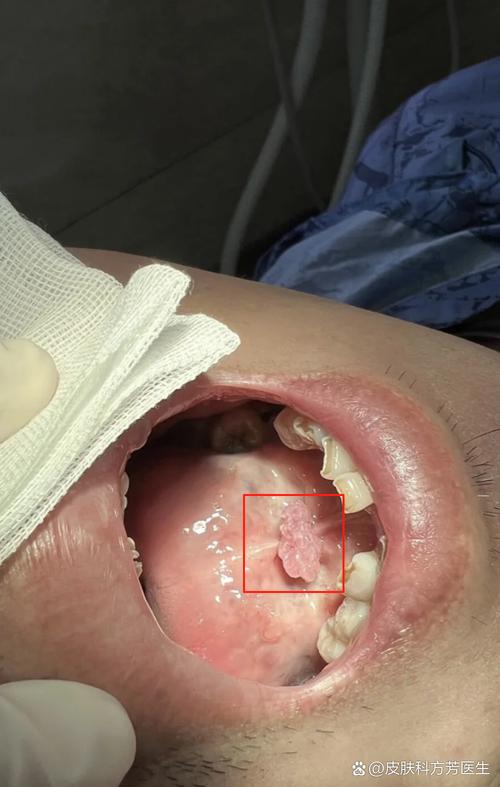

口腔乳头状瘤

这是最常见的口腔HPV感染表现。

- 外观特征:

- 形态: 呈小的、柔软的、菜花状或乳头状的疣状物。

- 颜色: 颜色通常与正常口腔黏膜一致,呈粉红色或白色。

- 大小和数量: 通常很小(几毫米),单个或成簇出现。

- 位置: 最常见于软腭、舌腹(舌头下面)、嘴唇内侧和牙龈。

- 患者感觉: 通常没有痛感,有时可能会因为摩擦或触碰而感到不适或出血。

- 图片示例描述: 你可以想象在口腔黏膜上长了一颗非常小的、柔软的草莓或花椰菜。